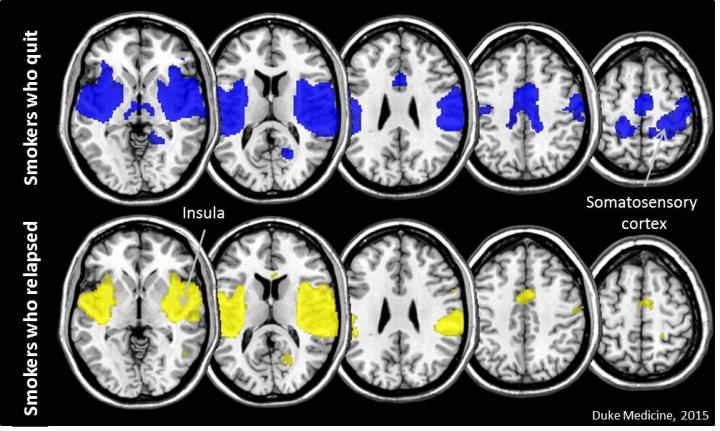

The researchers analyzed MRI scans of 85 people taken one month before they attempted to quit. All participants stopped smoking and the researchers tracked their progress for 10 weeks. Forty-one participants relapsed. Looking back at the brain scans of the 44 smokers who quit successfully, the researchers found they had something in common before they stopped smoking -- better synchrony (coordinated activity) between the insula, home to urges and cravings, and the somatosensory cortex, a part of the brain that is central to our sense of touch and motor control.

"Simply put, the insula is sending messages to other parts of the brain that then make the decision to pick up a cigarette or not," said Merideth Addicott, Ph.D., assistant professor at Duke and lead author of the study.

The insula, a large region in the cerebral cortex, has been the subject of many smoking cessation studies that show this area of the brain is active when smokers are craving cigarettes, said Joseph McClernon, Ph.D., associate professor at Duke and the study's senior author. Other studies have found that smokers who suffer damage to the insula appear to spontaneously lose interest in smoking.

"There's a general agreement in the field that the insula is a key structure with respect to smoking and that we need to develop cessation interventions that specifically modulate insula function," McClernon said. "But in what ways do we modulate it, and in whom? Our data provides some evidence on both of those fronts, and suggests that targeting connectivity between insula and somatosensory cortex could be a good strategy."